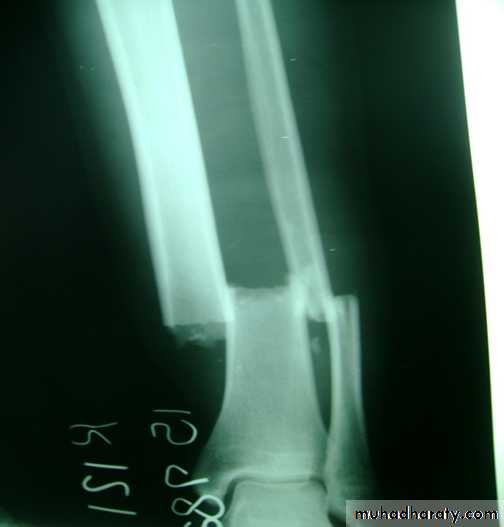

Slide 8 Bullet injury to lower leg1- What is the most dangerous infection suspected?2- What is the best treatment for such fracture?